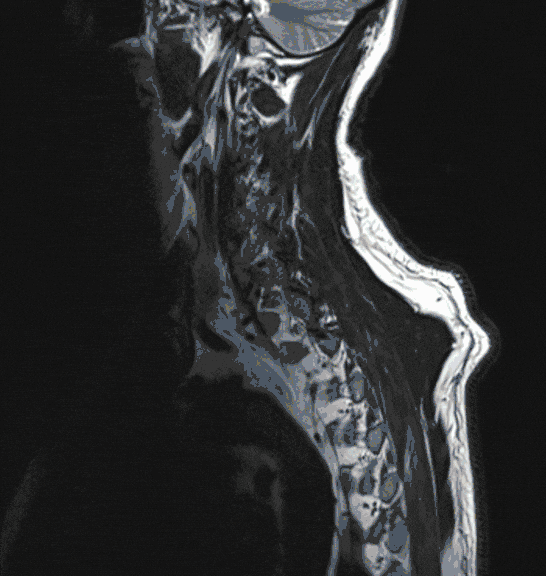

Meningeom

Meningeome sind nicht seltene Tumore, die das Rückenmark von außen bedrohen. Aufgrund ihres meist langsamen Wachstums können sie zu einer erheblichen Größe heranwachsen und dadurch die Funktion des Rückenmarks bedrohen. Sie werden deshalb meist spät erkannt, häufig erst nach Auftreten von starken Schmerzen oder Gangstörungen.